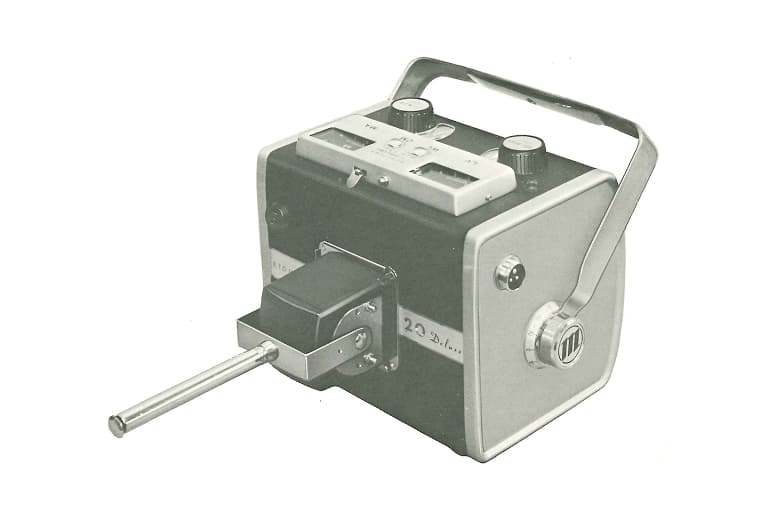

「携帯用X線発生装置」意匠登録(第248870号)

1965年

「アトムスコープ20D」東京都優良輸出商品として選定認証

「アトムスコープ20D」を中国・オーストラリアに初輸出

1970年

「アトムスコープ20D」東京都優良輸出商品として2度目の表彰

携帯型X線装置「アトムスコープHiD」